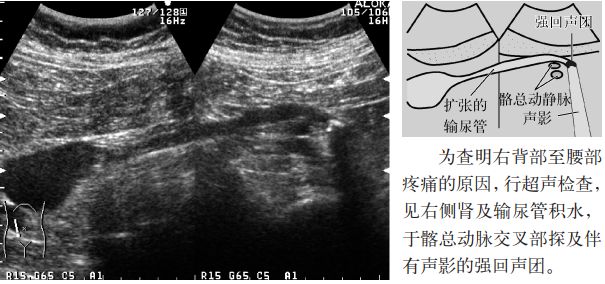

图3 肾结石

图11 输尿管结石(髂动脉交叉部)

1.大部分输尿管结石是肾结石掉入输尿管,大多数嵌顿于生理性三个狭窄部位:①肾盂输尿管移行部;②输尿管与髂总动脉的交叉部;③输尿管膀胱移行部,引起输尿管扩张(输尿管积水),几乎所有的病例均导致肾积水。